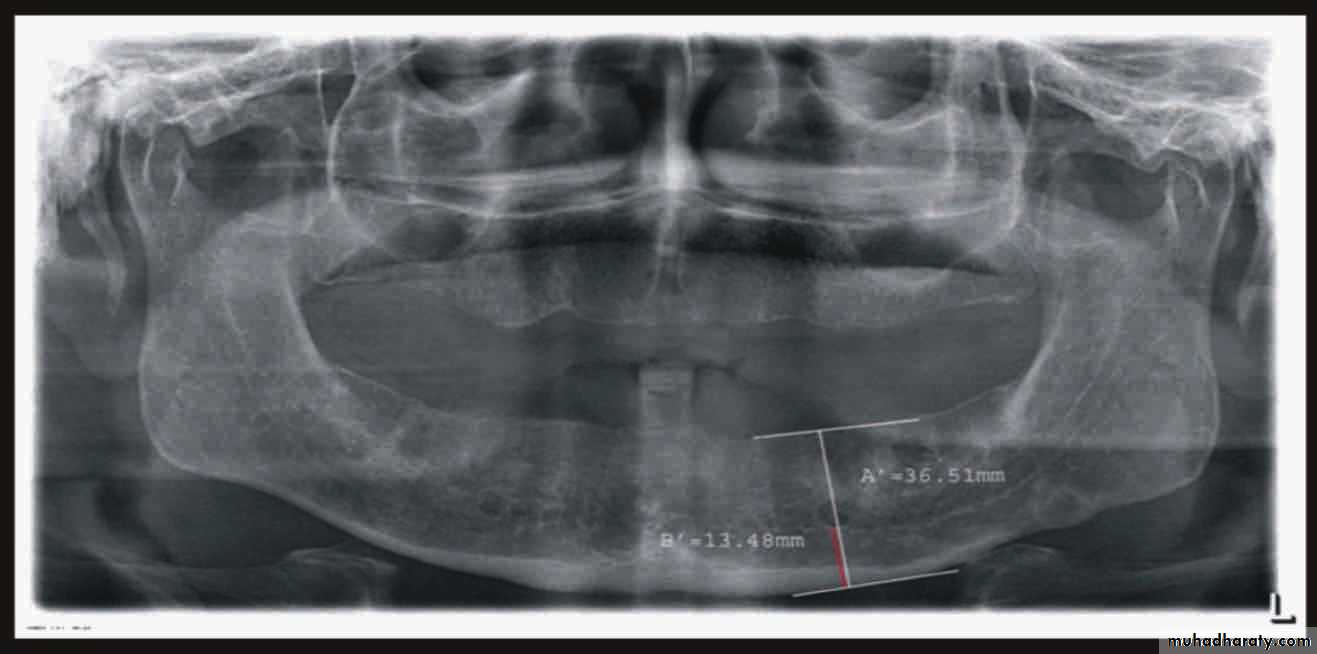

Radiographic examination:

• Cyst

• Tumor

• Retained root

• Periodontal condtion of remaining teeth

• Bone fracture

• Extend of bone resorbtion

• Locate cannal

• pt. education